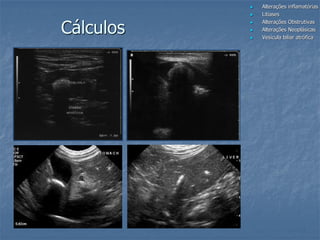

Cálculos

 Raros e nem sempre associados a

presença de sinais clínicos

 Estruturas hiperecogênicas produtoras de

sombra acústica variável

 com ou sem mobilidade

 Obstrução por cálculos em ductos são de

difícil diagnóstico

 Composição: colesterol, bilirrubina, calcio,

magnesio e oxalato

Colecistolitíase incomum

Gatos com cálculos radiopacos sem sombra acústica

Composição dos cálculos: colesterol e pigmentos biliares!